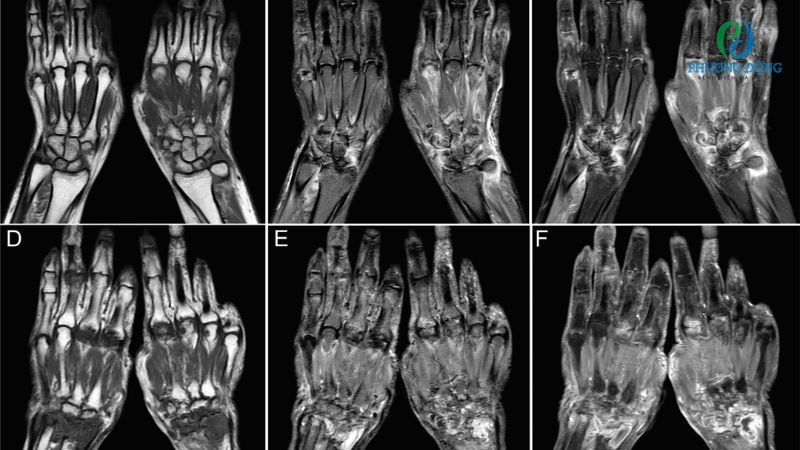

- Siêu âm, MRI với những trường hợp nghi ngờ có nang, u hoặc sưng quanh dây thần kinh.